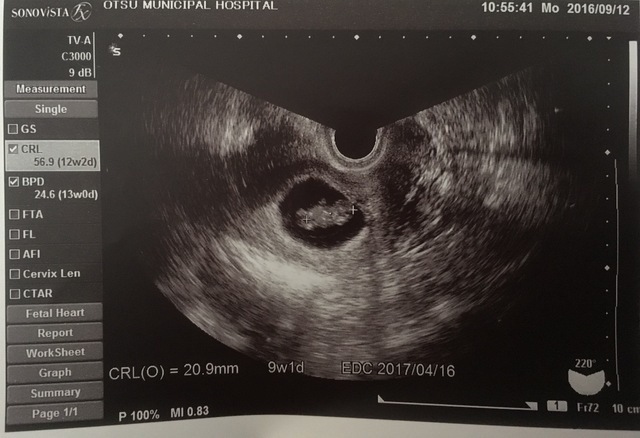

9週1日(9w1d・男の子)|プロ・カフェ さん(37歳)

エコー写真撮影時のエピソード:

初めての子どもでドキドキでした。人の形になってきたところで何となく人だなってわかりますよね。

つわりとかなかったので、焼肉屋とかにも行ってました。一般的につわりが治る頃に妊娠悪阻になって1週間寝たきりで救急で点滴してもらった思い出があります。